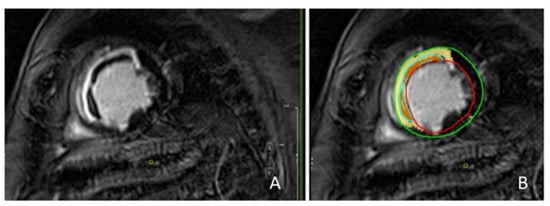

2.2. CMR Acquisition Protocol and Analysis